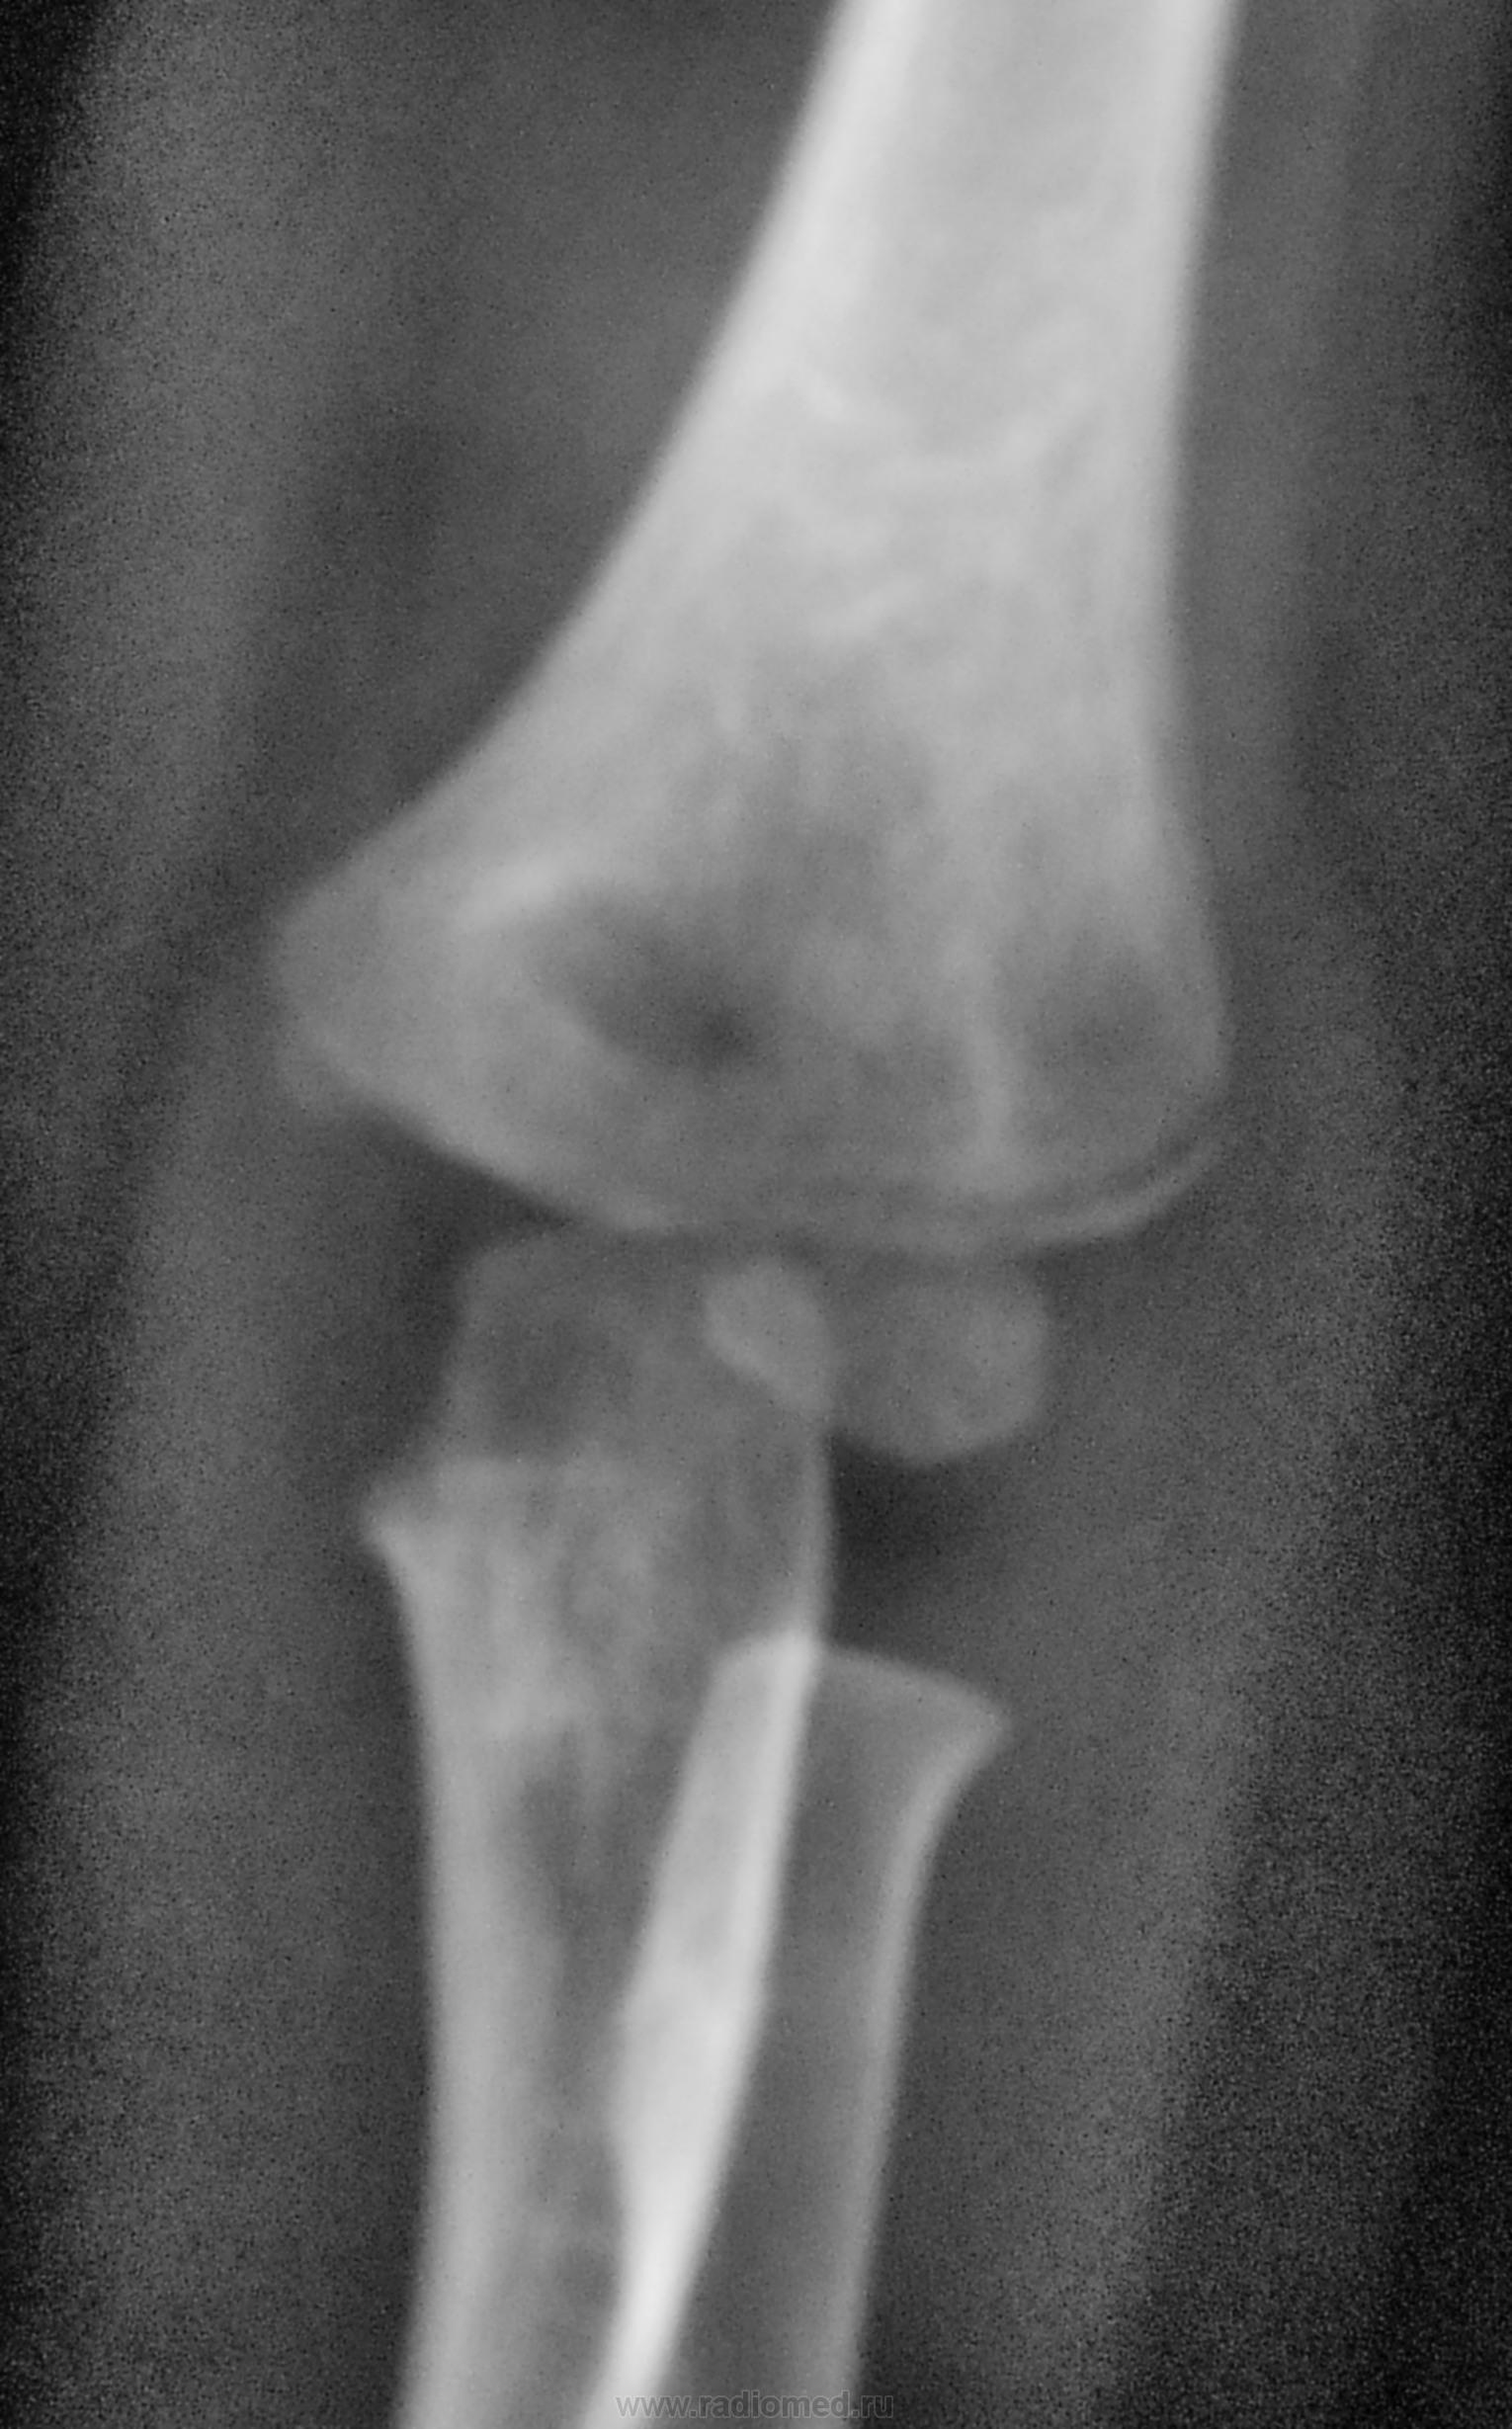

Пол пациента: Мужской пол Тип патологии: Травма Область исследования: Скелетно-мышечная система Методы исследования: Rg Травма. Пациент направлен на рентгенографию локтевого сустава https://radiomed.ru/sites/default/files/styles/case_slider_image/public/user/12/12.dscn0089a.jpg?itok=3NNM8UuI https://radiomed.ru/sites/default/files/styles/case_slider_image/public/user/12/13.dscn0090a.jpg?itok=sb-OhKYV https://radiomed.ru/sites/default/files/styles/case_slider_image/public/user/12/14.dscn0090ab.jpg?itok=Q4D_a_r1 ID:23259 Чт, 20/09/2012 - 21:19 #1 Сан Саныч1 Не на сайте Был на сайте: 11 месяцев 4 недели назад Зарегистрирован: 07.06.2010 - 21:17 Публикации: 2114 Вывих локтевой с эпифизеолизом локтевой и лучевой? Хочешь сделать что-то нормально - сделай это сам! Чт, 20/09/2012 - 23:16 #2 И.Бондаренко Не на сайте Был на сайте: 2 дня 6 минут назад Зарегистрирован: 13.09.2011 - 22:55 Публикации: 9206 Не работаю с детьми, поэтому вопрос: почему вывих локтевой? Вроде всё на месте. Эпифизеолиз согласен, только лучевой. Пт, 21/09/2012 - 14:50 #3 pronto Не на сайте Был на сайте: 1 год 2 месяцев назад Зарегистрирован: 22.02.2011 - 18:50 Публикации: 114 норма Пт, 21/09/2012 - 17:39 #4 Соломин Виталий... Не на сайте Был на сайте: 6 лет 7 часов назад Зарегистрирован: 04.04.2012 - 21:47 Публикации: 1096 pronto wrote: норма Почему-то при увеличении у меня снимки синие, ничего не понять. А если смотреть маленькие изображения (хотя может там чего-то не так разглядел) на возрастную норму похоже у маленького ребенка. Сб, 22/09/2012 - 10:02 #5 Dr.Yllich Не на сайте Был на сайте: 1 год 4 месяцев назад Зарегистрирован: 01.05.2011 - 22:52 Публикации: 1196 Остео-эпифизеолиз плеча (головчатого возвышения) без смещенияПриложения: С уважением. Ильич. Сб, 22/09/2012 - 10:08 #6 olle Не на сайте Был на сайте: 9 лет 9 месяцев назад Зарегистрирован: 07.10.2011 - 21:25 Публикации: 136 Мне кажется Dr.Yllich прав Сб, 22/09/2012 - 13:52 #7 Dr.Yllich Не на сайте Был на сайте: 1 год 4 месяцев назад Зарегистрирован: 01.05.2011 - 22:52 Публикации: 1196 Поддержка красивой девушки окрыляет. Спасибо! Ильич. С уважением. Ильич. Сб, 22/09/2012 - 13:56 #8 Катенёв Валенти... Не на сайте Был на сайте: 7 лет 1 месяц назад Зарегистрирован: 22.03.2008 - 22:15 Публикации: 54876 olle wrote: Мне кажется Dr.Yllich прав Мне тоже. Сб, 22/09/2012 - 20:08 #9 olle Не на сайте Был на сайте: 9 лет 9 месяцев назад Зарегистрирован: 07.10.2011 - 21:25 Публикации: 136 Пасибки, Yllich, я польщена... Сб, 22/09/2012 - 21:57 #10 Соломин Виталий... Не на сайте Был на сайте: 6 лет 7 часов назад Зарегистрирован: 04.04.2012 - 21:47 Публикации: 1096 Dr.Yllich wrote: Остео-эпифизеолиз плеча (головчатого возвышения) без смещения Рассмотрел «поближе». Похоже, все-таки ошибся, перелом плеча есть.

Вывих локтевой с эпифизеолизом локтевой и лучевой?

Не работаю с детьми, поэтому вопрос: почему вывих локтевой? Вроде всё на месте. Эпифизеолиз согласен, только лучевой.

Остео-эпифизеолиз плеча (головчатого возвышения) без смещения

Рассмотрел «поближе». Похоже, все-таки ошибся, перелом плеча есть.